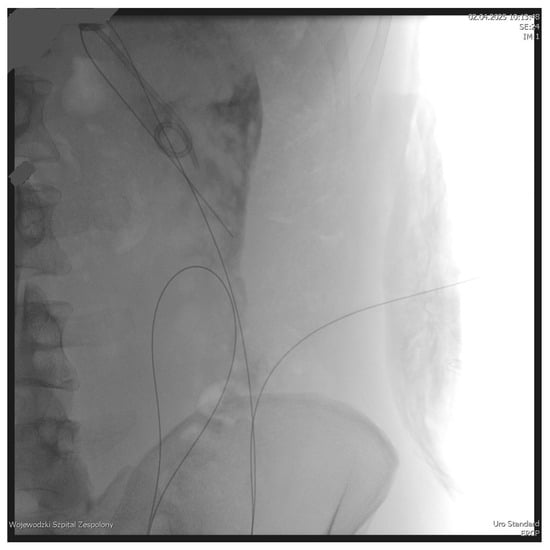

The PEN procedure was performed under general anesthesia with endotracheal intubation in the supine position. Percutaneous endoscopic necrosectomy was performed under the guidance of ultrasound (using a Logiq P9, convex C1-6 MHz probe) and fluoroscopy. Following the establishment of percutaneous drainage, Cook Medical Acrobat 2 AWG2-35-45 guidewire was inserted and looped inside the lumen of the necrotic collection (Figure 1 and Figure 2) to be followed by implantation of a fully coated self-expandable Evolution® esophageal controlled-release stent 120 mm or 150 mm in length and 20 mm in diameter (Figure 3 and Figure 4). A flexible Evis Exera III CF-H190L endoscope–gastroscope (Olympus) was then inserted into the necrotic collection through the lumen of the esophageal stent, and a percutaneous endoscopic necrosectomy procedure involving mechanical removal of necrotic tissue from the collection under direct endoscopic image guidance was performed (Figure 5, Figure 6 and Figure 7). A Dormia basket (Figure 8) was used to remove necrotic tissue. In the course of the percutaneous endoscopic necrosectomy procedure, the necrotic collection was extensively flushed with physiological saline, and the contents from the reservoir were aspirated. The PEN procedure was considered complete upon removal of demarcated necrotic tissues or upon bleeding from the inflammatory granulation tissue within the necrotic collection. If subsequent percutaneous endoscopic necrosectomy procedures were required in the same patient, the esophageal stent was left in the percutaneous position, and one or two 16 Fr silicone drains (depending on the size of the collection) were inserted into the lumen of the necrotic collection through the stent to maintain patency. The drain(s) were used to flush the collection with 100 mL of physiological saline 6 times a day. Following the completion of endoscopic treatment using percutaneous access, the esophageal stent was removed, and the stenting site was secured with a stoma bag to drain the remaining contents from the residual necrotic collection (Figure 9).

Figure 1. Looped guidewire within the lumen of the WOPN cavity. Source: Department of General, Gastroenterological, and Oncological Surgery, L. Rydygier Regional Hospital in Toruń.

Figure 2. Guidewire percutaneously inserted into the lumen of the WOPN collection. Source: Department of General, Gastroenterological, and Oncological Surgery, L. Rydygier Regional Hospital in Toruń.